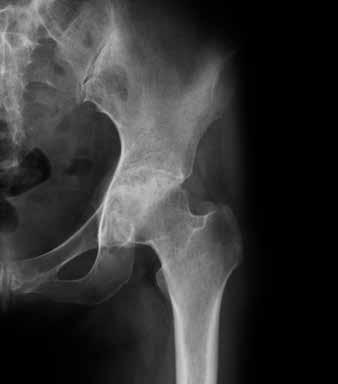

Articolazione artrosica dell’anca

Articolazione sana dell’anca

Nel tempo l’artrosi si sviluppa in modo molto diverso da persona a persona. Può colpire una o più articolazioni. Allo stadio iniziale, poi, è difficile prevedere se ci si deve aspettare dolori, rigidità o limitazioni motorie. A volte gli esami radiologici evidenziano alterazioni marcate, ma la persona colpita se ne accorge appena nella sua vita quotidiana. Viceversa, è possibile che una persona avverta forti dolori senza che la radiografia evidenzi degenerazioni importanti.

A tutt’oggi non è ancora chiaro quali siano i fattori che influenzano l’entità dei disturbi. È importante sapere, però, che una diagnosi di artrosi non vuol dire automaticamente che bisogna aspettarsi forti limitazioni in futuro.